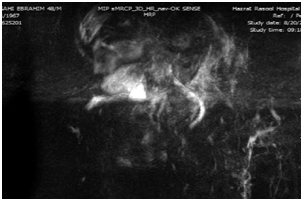

Finally, liver biopsy was done .The sample was stained with Hematoxylin, and Eosin, Trichrome and Reticulin. Extensive lobular architecture disarray with marked necro-inflammatory changes of parenchyma characterized by obvious hydropic changes and single cell necrosis of hepatocytes as well as infiltration of mixed inflammatory cells was shown in Hematoxylin, and Eosin staining (Figure 2). Collapse of reticulin network associated with psuedolobule formation as well as portal fibrosis was shown in Reticulin and Masson-Trichrome staining (Figures 3&4). Overall findings were in favour of an acute/sub acute liver injury according to Modified HAI score grade: 14/18, stage: 3/6.

Figure 3 (Reticulin X100). Collapse of reticulin network associated with portal fibrosis.

Figure 4 (Trichrome X40) Collapse of reticulin network associated with portal fibrosis.